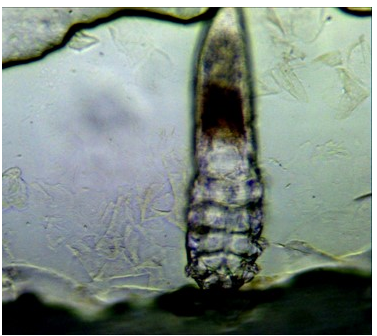

蠕形螨

蠕形螨 寄生于人体的蠕形螨有毛囊蠕形螨和皮脂蠕形螨。两种蠕形螨生活史相似,发育过程有卵、幼虫、前若虫,若虫和成虫5期。

毛囊蠕形螨图片: